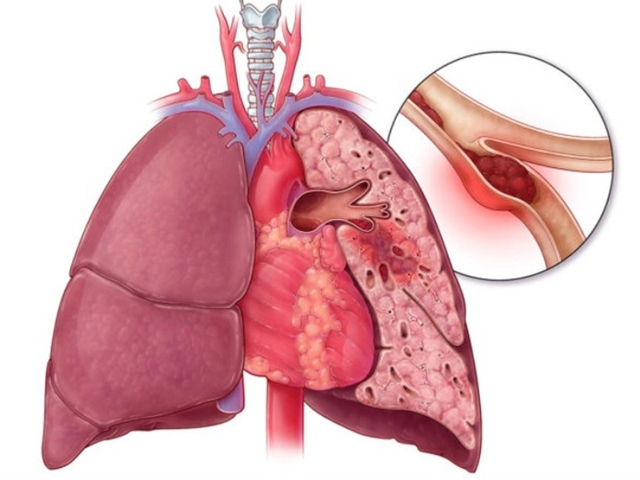

При варикозном расширении вен повышается вероятность рецидива развития тромбов. Если камни мигрируют и попадают в воротную вену – это опасное осложнение. Это может привести к эмболизации легких, которая имеет тяжелые последствия.

Врачи считают флеболиты безвредными для человека, за исключением случаев риска рецидива окклюзии. Варикоз, осложненный флеболитиазом, усиливает вероятность повторного тромбирования. Миграция конкрементов в воротную вену способна стать триггером ТЭЛА с летальным исходом.

Мигрирующие обызвествления, попавшие в воротную вену, способны стать источником легочной эмболизации с достаточно серьезными последствиями, вплоть до летального исхода.